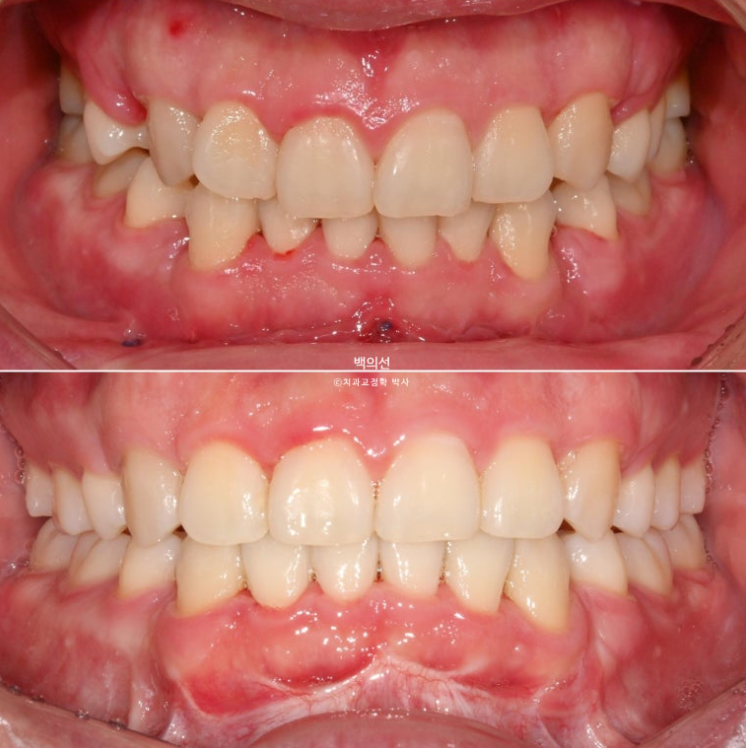

전 후 비교 보겠습니다.

24.10~25.08

남아있던 공간은 추가장치로 깔끔히 없어졌습니다.

앞니가 깊게 물리는 과개교합도 좋아졌습니다.